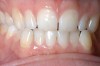

The first signs of tooth wear may not be immediately recognizable because changes to the enamel surface can be difficult to diagnose. The mamelons on the incisal edge of incisors wear away within the first decade after eruption, but other less obvious changes also occur (Figure 1). The cusp tips of molars and premolars may flatten as may the facial surfaces of upper incisors. If allowed to progress, eventually the enamel is worn away, exposing small areas of dentin (Figure 2). Dentin exposure is much easier for dentists to recognize, but it means that considerable amounts of the tooth have been lost. Ideally, therefore, early diagnosis should help to prevent the lesion from progressing into dentin. If the process of tooth wear continues without intervention, almost total destruction of the tooth can occur (Figure 3).

Figure 1  Early enamel loss and some dentin exposure along the cervical margins of the teeth. The cause in this case was identified when the patient admitted to toothbrushing immediately after drinking pure orange juice.

Figure 1